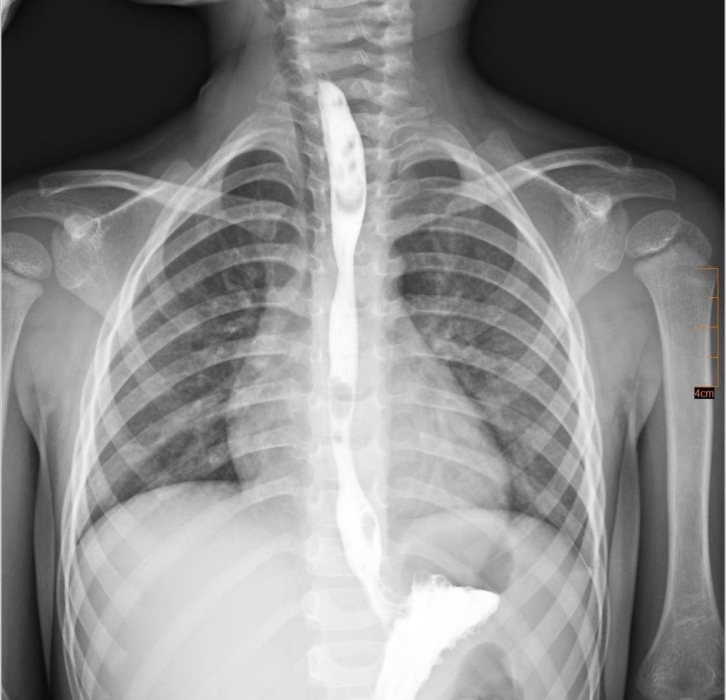

Во Львове врачи спасли 3-летнего мальчика, который случайно проглотил средство для очистки бытовой техники от жира и получил тяжелый химический ожог пищевода.

Лечение длилось в течение двух лет. На момент госпитализации малыш находился в крайне тяжелом состоянии: он не мог самостоятельно есть, страдал от сильной боли, активного слюнотечения и рвоты.

Через некоторое время у мальчика развился критический стеноз пищевода - значительное сужение его просвета, что полностью исключало прием пищи через рот.

Мультидисциплинарная команда, после тщательного обсуждения, приняла решение о проведении серии баллонных дилатаций пищевода. Это малоинвазивные эндоскопические вмешательства, во время которых суженный участок постепенно расширяют специальным баллоном без выполнения разрезов.